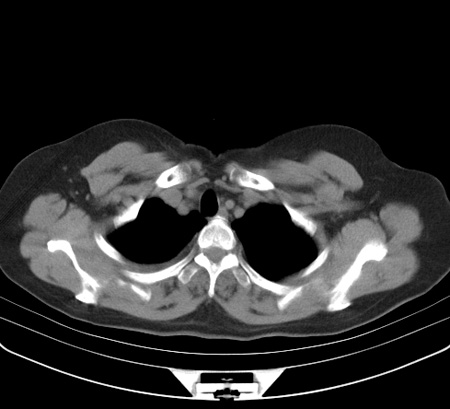

以下是引用余辉在2009-2-19 20:10:00的发言:[br]多考虑急性感染性病变,右中叶尚可见多枚小斑片状影,多为化脓性肺炎,双侧胸腔积液

以下是引用随光逐影在2009-2-19 20:33:00的发言:[br]1)考虑右肺炎症;建议抗炎治疗后复查。2)双侧胸腔积液(以右侧为甚)。

以下是引用花凤凰在2009-2-19 20:46:00的发言:[br]病人有发热,胸痛急性起病,主要病变位于右肺中叶外侧段,呈楔行改变,位于外带胸膜下,考虑为肺梗塞可能!!!!!!!!!!!!!!!!!!!!!!!!!!!!!!!!!!!